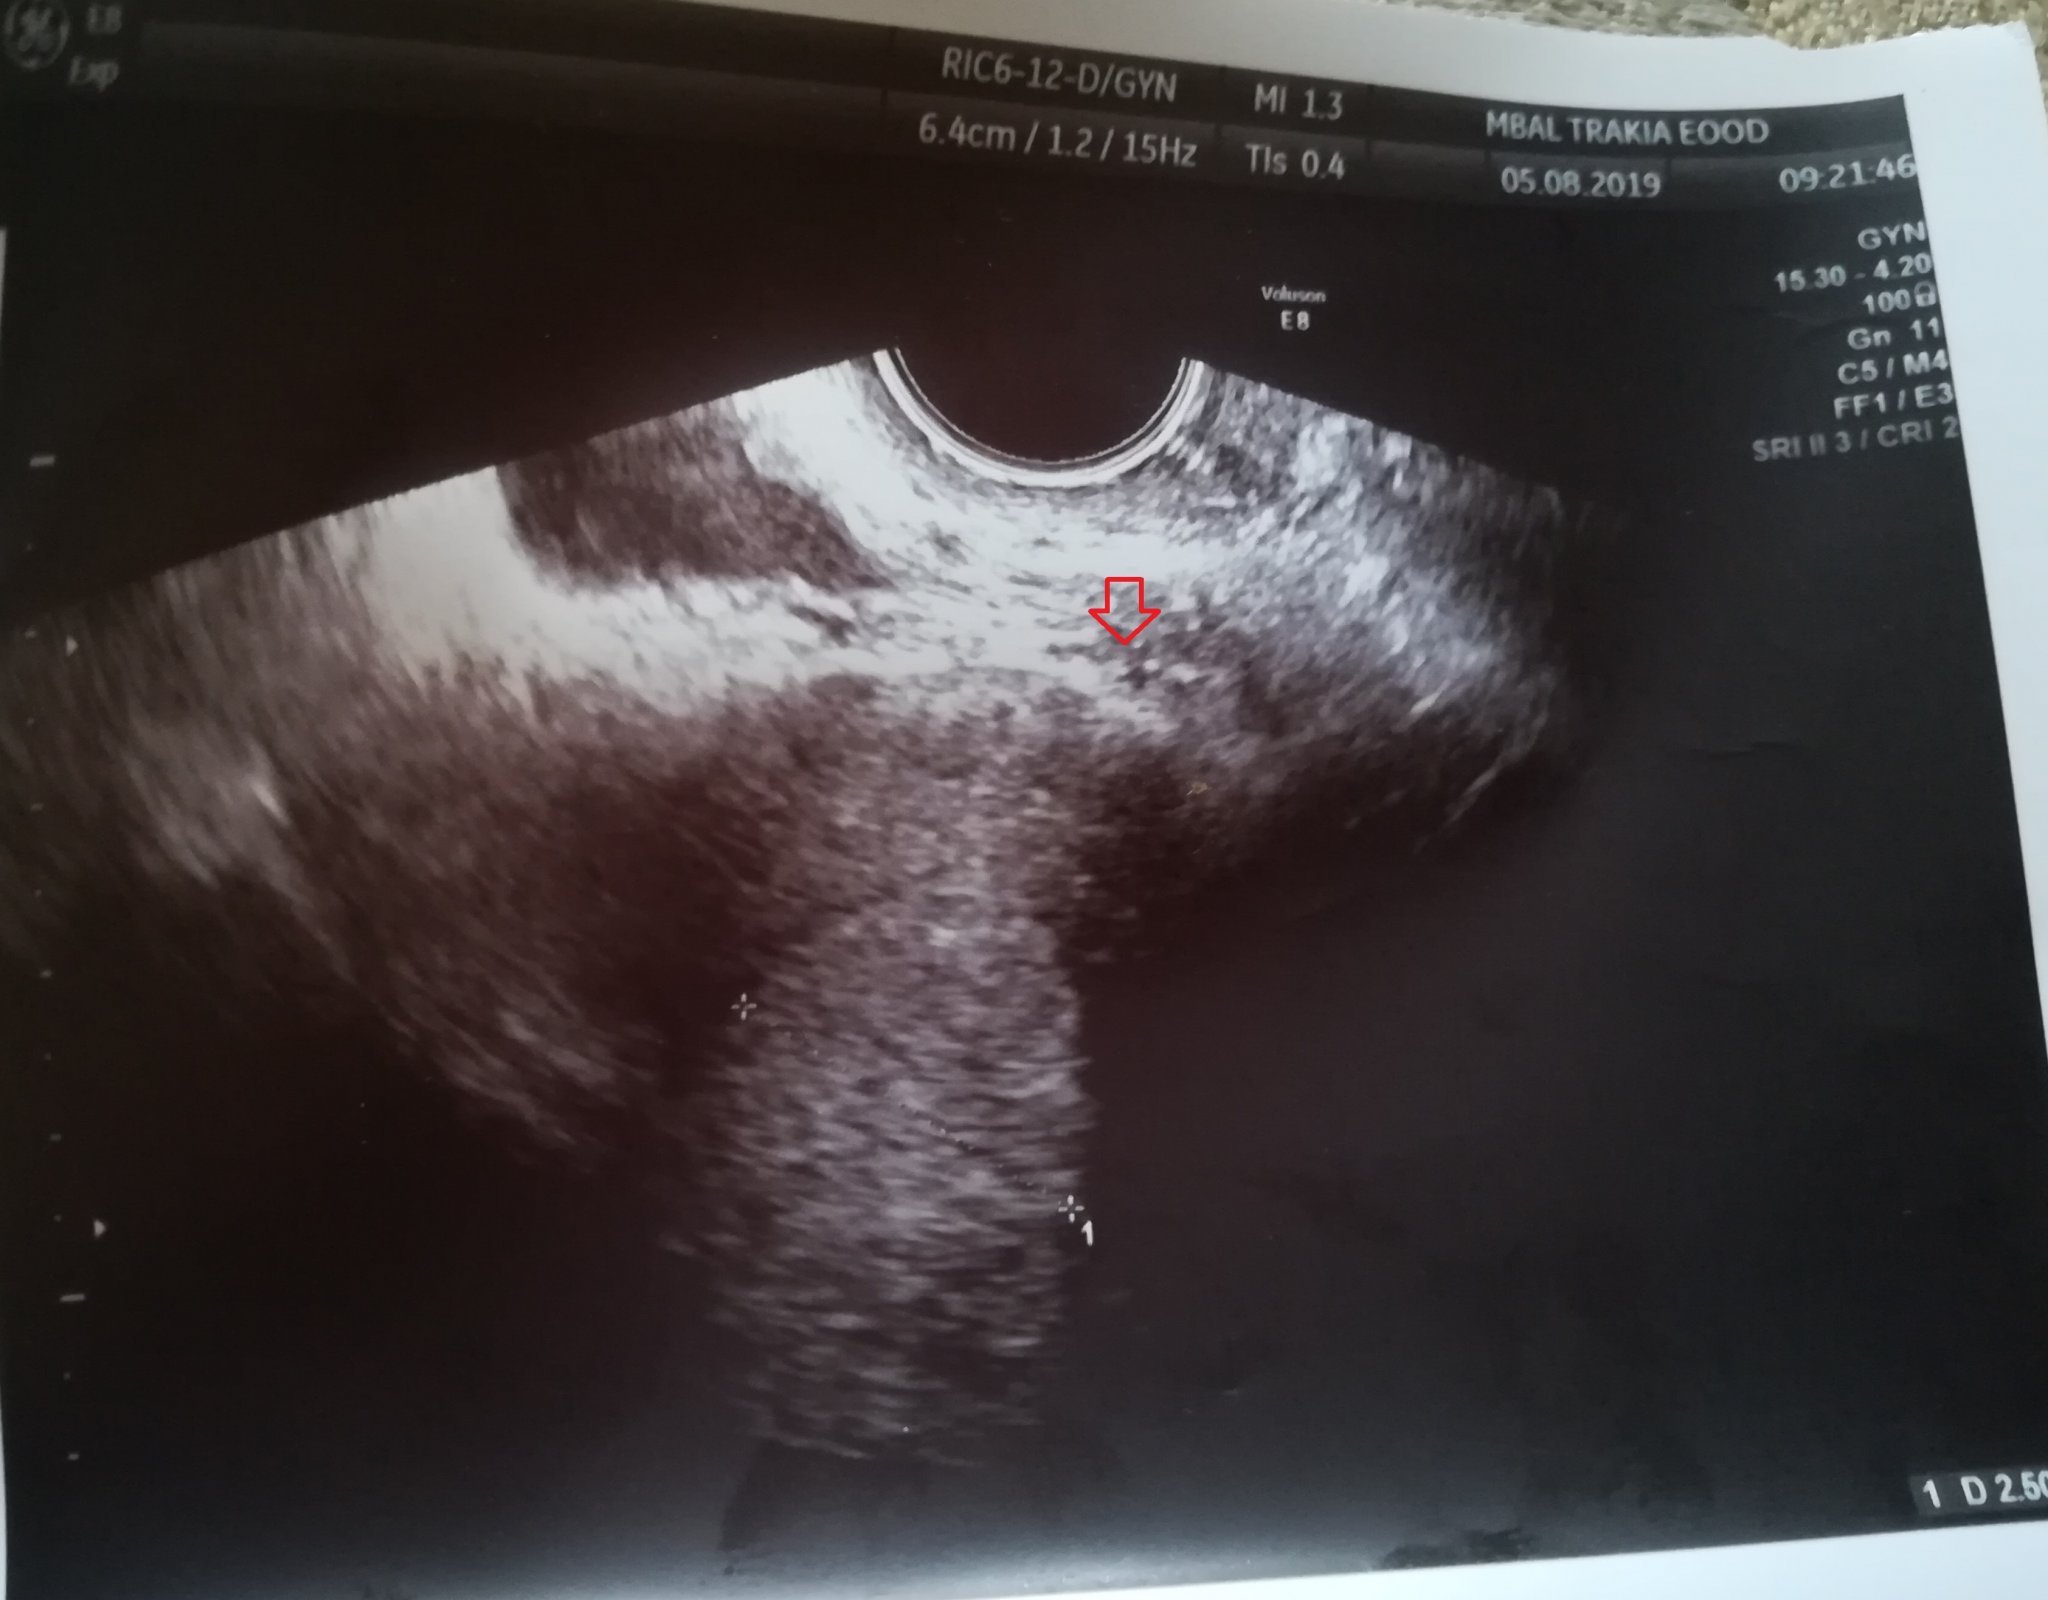

Хайде да ви хвърля пак в оркестъра, че и аз съм там. Днес бях на гинеколог, още сутринта. Изплаках си болката колко дълго чакаме бебе и , че го няма и какви ли не лоши мисли не ми минават през главата. Една от които е , че няма да стане без специална намеса. Започна прегледа, каза че имам увеличен влагалищен секрет, взе ми цитонамазка и хоп на кушетката за ултразвук ( вагинален) . Бърка жената, чуди се нещо, нищо не казва. ( А кабинета е страхотен, над кушетката има монитор и каквото вижда тя, го вижда и пациента. И аз гледам ,ама нищо не разбирам. Казва нещо там на сестрата. Обяснява каква ми била матката. Казвам, че имам някакви бодежи последните дни в десен яйчник, несигурно каза, че вижда някакво фоликулче, нещо там... Викам ей това е сигурно задържан фоликул. Продължава да човърка, няколко пъти връща на едно и също място, пита ме кога ми е дошло последно, погледна пак тестовете за ову и само каза "а ти нямаш закъснение още"....... ????..... накрая си цъкна снимка. После ми обясни, че вижда нещо, но не може да каже още какво е , защото е много малко. Каза да изчакам до 09.08 , когато ще отида за резултатите от изследването. Каза, че е хубаво да пусна и един бетаЧХГ да се види такова ли е, за каквото тя се съмнява. Показа ми точката за която се съмнява. Каза, че стиска палци да се е случило този път.

Абе да питам само аз ли виждам и други точки като тази или не? Това ме учудва много. Верно, че е по-тъмничка, ама как да и повярвам като има точки по цялата снимка

И аз виждам много точки . Обаче преди закъснение , няма как да се види каквото и да е било ...

Само информативно, за да се види нещо в матката, дори СЯНКА на сак(при мен видяхме първо сянка и след 3 дни сака) чхг трябва да наближава 1000.

Ако днес е видяла нещо твоята АГ кръвния тест трябва да е категоричен. А пикливия с доста по ясна черта. Не искам да звуча гадно, просто това е чиста информация, без захаросани надежди.